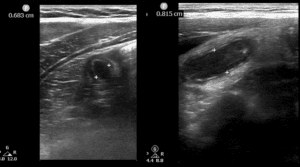

A 7-year-old female presented with several hours of abdominal pain and emesis, without fever or diarrhea. Visual Analog Scale (VAS) was not recorded. She had right lower quadrant tenderness, without peritoneal findings. White blood cell (WBC) count was 11.8 K/micron, and neutrophil count 10.3 K/micron. POCUS was read by the pediatric emergency fellow as unremarkable, but was flagged on quality assurance review as showing a 7-millimeter appendix surrounded by inflamed fat (Figures 1 & 2). She was discharged from the PED.

Figure 1. 7-millimeter noncompressible appendix in long-axis.

Figure 2. Appendix, noncompressible, in short-axis, surrounded by echogenic mesenteric edema/ inflammation. The arrow’s tip sits on a small amount of free fluid surrounding the tubular appendix. The star sits in the center of a cloud of echogenic inflamed fat.